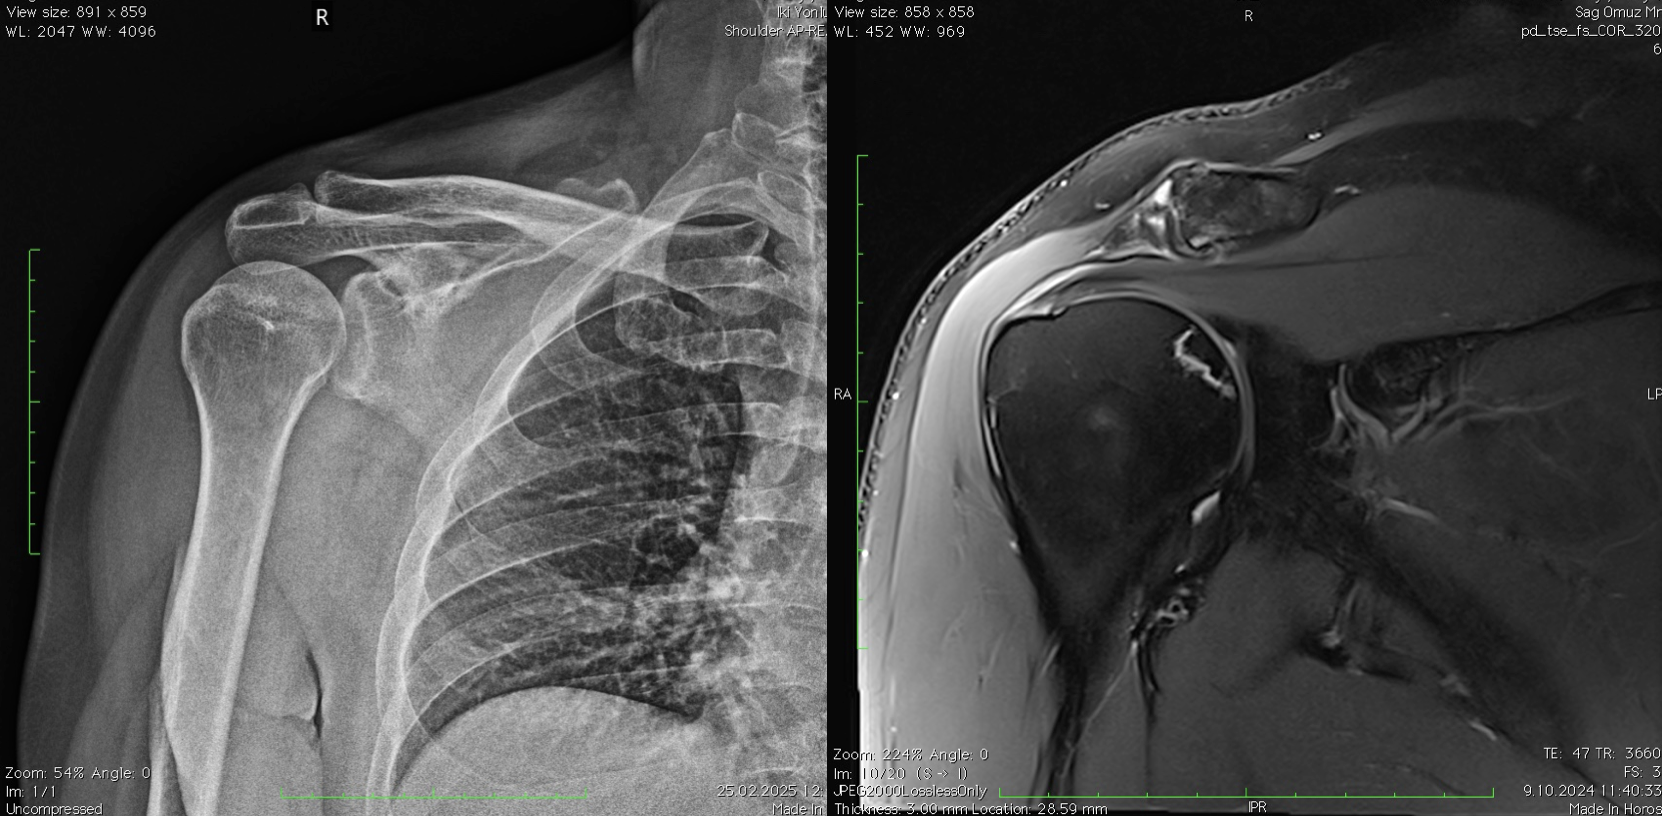

- Tanı: Röntgende bulgu görülmez, ancak MR’da beslenme bozukluğu ve ödem izlenebilir.

- Belirti: Röntgende kemikte sertleşme (skleroz). MR’da çürüme hattı ve çevresinde belirgin kemik iliği ödemi görülür.

- Belirti: Ağrı ve hareket kısıtlılığı artar. Çökme kırıkları ve yalancı kistler görülebilir.

- Röntgen (X-ray): İleri evrelerde değişiklikleri gösterir.

- MRI: Erken evre teşhis için en duyarlı yöntemdir.

- BT (Tomografi): Kemik çökmesi derecesini değerlendirmede kullanılır.